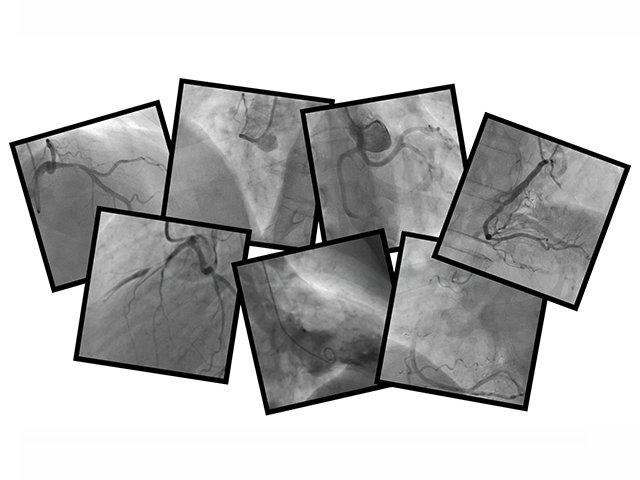

80 minutes Angiography Recorded on 24th Mar 2016 This webinar was a huge success. It will boost your understanding of how to read and interpret angiograms.